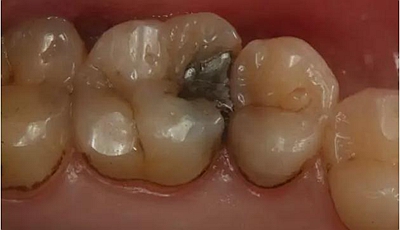

患者男性,35歲,B6銀汞充填后食物嵌塞,要求重新充填,口內(nèi)檢查見B6近中鄰頜面銀汞充填物,局部缺損,有繼發(fā)齲,去除原充填物及繼發(fā)齲,發(fā)現(xiàn)齲壞位于牙齦下方,給予冠延長手術,同期嵌體預備,后一次性取模。(同樣設計為齦上邊緣)

硅橡膠取模后,灌注模型,科爾琥珀樹脂制作嵌體。